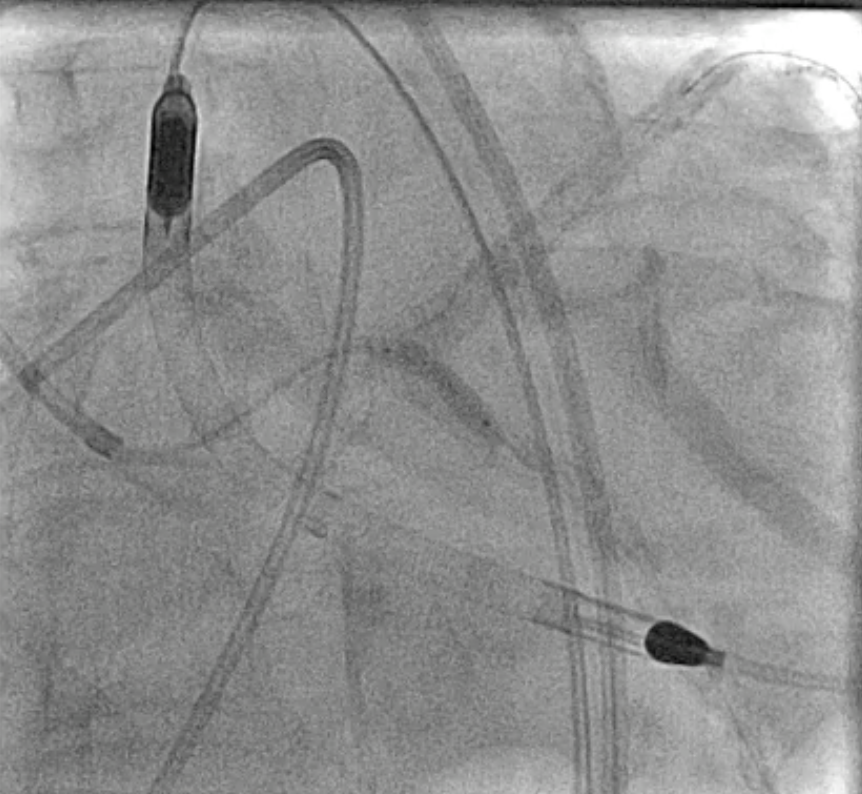

An Impella CP was inserted via the right femoral artery for hemodynamic support (baseline CI 2.07 L/min/m©÷, PCWP 34 mmHg). The LM was engaged with a 7 Fr EBU 3.5 guiding catheter. Angiography demonstrated heavily calcified distal LM bifurcation ISR with multiple stent layers extending into both LAD and LCX. Rotational atherectomy (RA) using a 1.5-mm burr was first attempted at the LAD-distal segment, but severe calcification prevented smooth burr passage even under Dyna mode. After changing to a 2.0-mm burr, the lesion was successfully crossed and adequately modified. Subsequently, the 1.5-mm burr was redirected for LCX lesion debulking, but burr entrapment occurred at the proximal LCX during the third run. Hemodynamics remained stable under Impella support. The burr was freed using a combination of deep seating a Guideplus ST for additional backup, small-balloon anchoring, and gentle forward–reverse rotation maneuvers. To ensure complete plaque modification, a 2.0-mm burr was used again to finalize both LAD and LCX runs. Cutting balloon angioplasty yielded suboptimal expansion; therefore, intravascular lithotripsy (IVL 3.5 mm, ≈40 pulses per ostium) was applied to achieve calcium fracture and full balloon compliance. Lesions were treated with DEB 4.0¡¿30 mm LM–LAD and 3.0¡¿30 mm LCX, followed by kissing balloon inflation. The Impella was removed uneventfully, and the patient recovered without hemodynamic compromise. Final angiogram showed well-apposed stents.